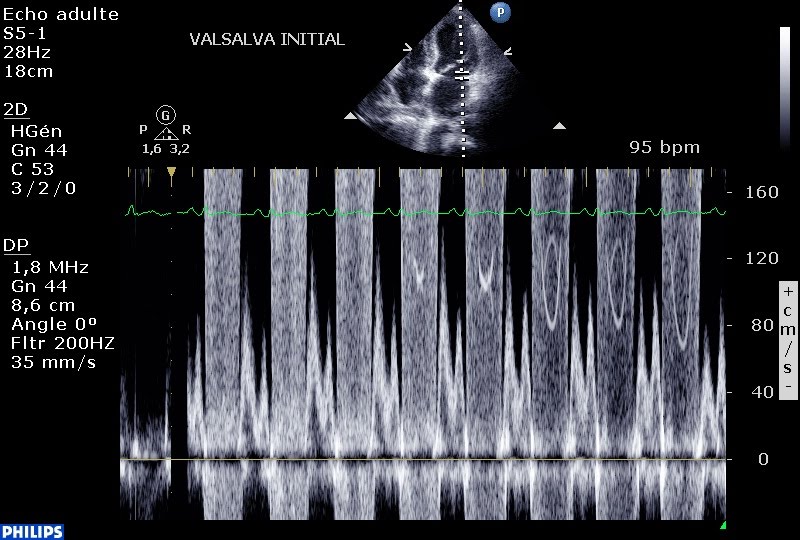

Incrédule, je tente une manœuvre de valsalva qui se divise en 4 étapes:

1- majoration brève de la précharge en vidant les veines pulmonaires sur l’hyperpression thoracique,

2- Augmentation de la pression intra-thoracique et donc diminution de la précharge,

3- Le relâchement engendre une expension brutale de l’aorte et de l’AP qui engendre une chute du débit cardiaque et du remplissage pendant 20 secondes,

4- Retour veineux augmenté et débit cardiaque augmenté pendant 20 secndes; avant un retour à l’état de base.

Etape 2 : L’IM augmente bien (noter la densité du flux Doppler continu) alors que le retour veineux est diminué!